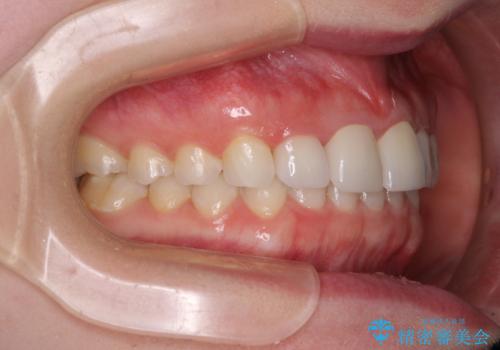

- 前歯の歯並びと虫歯を気にして来院された患者様です。

上下前歯の歯列不正はインビザラインにより歯列を整え、その後に、前歯5本をオールセラミッククラウンにて補綴治療することとしました。

矯正治療前に前歯のむし歯治療を行ったものの、樹脂で充填するには虫歯が広範囲であったため、審美的に問題がありました。

矯正治療にて歯並びを整えた後に、虫歯の大きかった5本の歯をセラミッククラウンにて補綴し、明るい口元になりました。